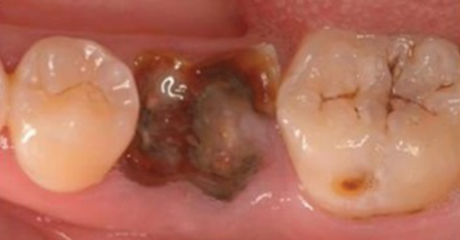

치아가 녹아버리거나 부러져버리는 상황에 이르게 됩니다.

신경제거 후 신경으로부터 받던 영양분을 공급받지 못해 약해진 치아는 작은 충격에도 금이 가거나, 부러지거나, 깨져버리기 때문에 단단한 크라운을 씌워 치아를 보호해야 합니다.